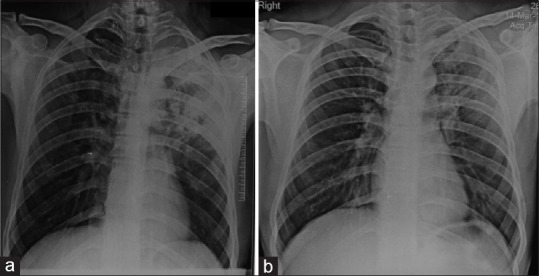

Methods: The study was conducted in a 1250-bedded North Indian hospital. Consecutive consenting adults admitted with CAP over a period of 2 years from July 2019 were enrolled for the study. The patients were subjected to routine investigations and radiological imaging and treated with standard antibiotic/antiviral therapy as per standard protocols and followed daily till clinical resolution and discharge from the hospital. Serial chest radiographs were taken at 2, 4, 8, and 12 weeks after admission, and the follow-up terminated at either complete clinical or radiological resolution.

Results: 176 patients (age 20 to 90 years, median 60 years; 109 (61.9%) male) participated. Eighty-nine (50.6%) patients were current smokers. Chest radiographs revealed lobar consolidation as the most common finding (n = 97, 55.1%), followed by pulmonary infiltrates (n = 73, 41.5%) and pleural effusion (n = 6, 3.1%); 44 (25%) patients had multi-lobar consolidation The rates of radiological resolution at 2, 4, 8, and 12 weeks follow-up were 30%, 38.5% (cumulative 68.5%), 25.7% (cumulative 94.2%), and 5.9% (cumulative 100%) of patients, respectively. The average time taken for radiological resolution was 31.49 (±20.2) days in 70 cases, where documented. On multi-variate analysis, smoking was an independent factor for delayed radiological resolution (P = 0.007).

Conclusion: Radiological resolution of CAP occurs in the majority (68.5%) of the patients at 4 weeks from the time of clinical presentation, with smoking as an independent risk factor for delayed (>4 week) radiological resolution. Clinicians can wait for 4 weeks to document radiological recovery unless clinical features suggest otherwise.